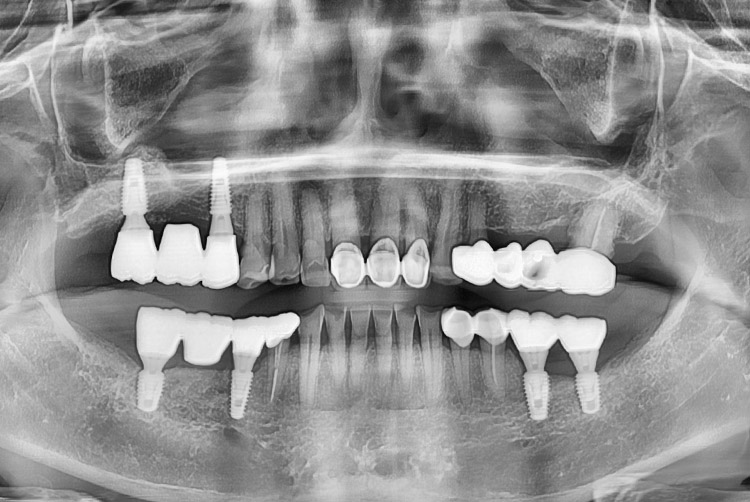

[임플란트] 임플란트

치료후 : 2022-05-26

세종치과는 많은 환자와 다양한 케이스를 바탕으로 항상 편안한 임플란트 수술을 제공하고자 노력하고,

오래동안 튼튼히 쓸 수 있는 임플란트 수술을 가장 큰 목표로 삼고 있습니다